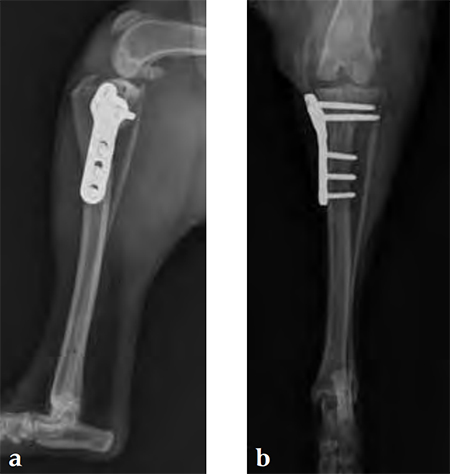

Case 1: English bulldog

A 4-year-old, female, spayed, 33 kg English bulldog had a CrCL tear and a medial patellar luxation. The small stature 3.5 mm TPLO plate was perfect for this dog due to the small profile of the bone and the need to use a heavier plate (3.5 vs a 2.7 mm). In the past, veterinary surgeons have been forced to either squeeze the standard TPLO 3.5 mm plate on the bone or use an undersized TPLO 2.7 mm plate. In this patient, the shorter and smaller profile head of the small stature TPLO 3.5 mm was perfect.